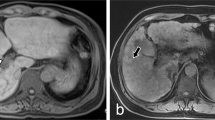

All subjects underwent 4D flow MRI using a clinical 3-T scanner (Skyra; Siemens Healthcare, Erlangen, Germany) with a 32-channel phased array coil. The 4D flow sequence covered the main PV (Fig. 5) and utilized both ECG-gated and navigator-triggering techniques. The imaging parameters for 4D flow MRI were as follows: repetition time/echo time = 6.72/2.84 ms, field-of-view = 380 × 308 mm2, slice thickness = 2.0 mm, matrix = 192 × 129, GRAPPA acceleration factor = 3, Cartesian sampling of k-space, number of excitations = 1, and scan time = 8–15 min. Four-dimensional flow MRI scans were performed after a period of fasting for at least 8 h, and the status of the stomach was reviewed on anatomic MR images (Fig. 5a). To avoid velocity aliasing, the velocity encoding was performed prior to the 4D flow MRI. Through the velocity-encoding sensitivity [VENC] scout images (Fig. 5b), the VENC was set to 30 cm/s18.

Anatomic coronal MR image (a) in the abdomen showing the main portal vein (PV) and the status of the stomach. Velocity-encoding (VENC) image (b) focusing on the PV (VENC = 30 cm/s). The red dotted circle indicates the cross-sectional area of the PV. Four-dimensional flow MRI data were post-processed; then, segmented anatomic images (left) and color-coded streamline images (right) were generated from a 38-year-old male (c), a 45-year-old female (d), a 53-year-old male (e), and a 68-year-old female (f). The red solid lines in (c) indicate planes for measuring the hemodynamic parameters, and the white arrows in (c) show the direction of blood flow.